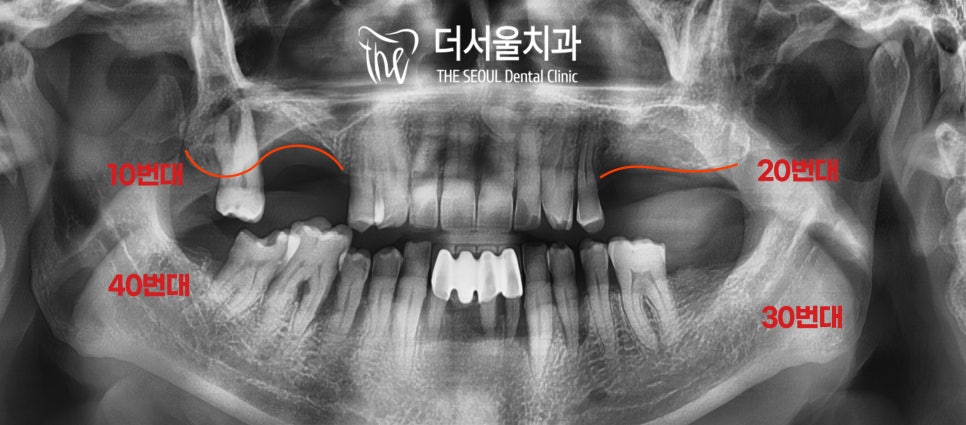

환자의 구강 내를 살펴봤는데요.

네.. 일단 전반적으로 상황이 좋지 않네요.

군데군데 썩어있는 치아들과

홀랑 빠져버린 곳 그리고 정출까지..

위쪽은 누가 봐도 골소실이 심해 보였는데요.

파노라마 사진을 찍어 확인해 봤더니

뼈가 너무 없네요..

# 16은 골소실이 너무 심해서

컴퓨터 모의수술 상에서도 무리인듯합니다.